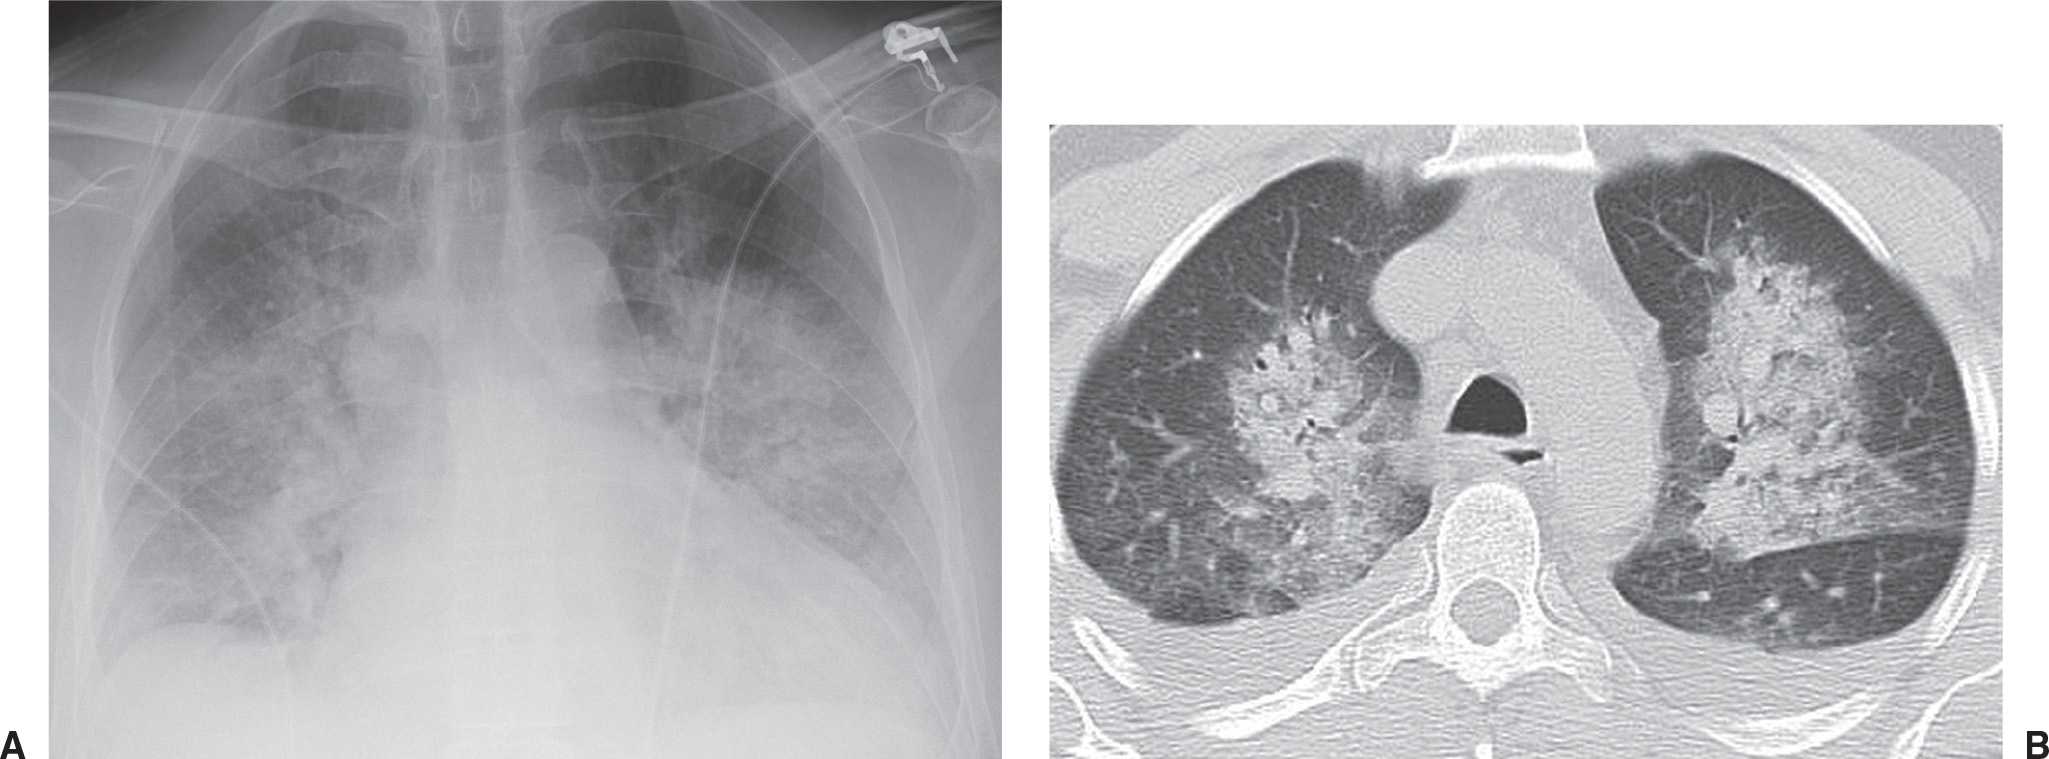

Pulmonary edema CT wikidoc Alveolar Oedema This fluid collects in the many air sacs in the lungs,. This process leads to diminished gas exchange at the alveolar level,. It can sometimes have a central. Pulmonary edema can be defined as an abnormal accumulation of extravascular fluid in the lung parenchyma. Pulmonary edema is a condition caused by too much fluid in the lungs. Pulmonary edema is. Alveolar Oedema.

From radiopaedia.org

Image Alveolar Oedema Pulmonary edema can be defined as an abnormal accumulation of extravascular fluid in the lung parenchyma. Alveolar oedema is caused by fluid leaking from the interstitial tissues into the alveoli and small airways, and manifests as airspace shadowing (consolidation) It can sometimes have a central. Pulmonary edema is the accumulation of excessive fluid in the alveolar walls and alveolar spaces. Alveolar Oedema.

From www.semanticscholar.org

Figure 1 from Imaging findings of pulmonary edema Part 1. Cardiogenic Alveolar Oedema Pulmonary edema is the accumulation of excessive fluid in the alveolar walls and alveolar spaces of the lungs. This process leads to diminished gas exchange at the alveolar level,. Pulmonary edema can be classified into four categories based on these physiologic determinates of edema: Pulmonary edema is a condition caused by too much fluid in the lungs. Pulmonary edema can. Alveolar Oedema.